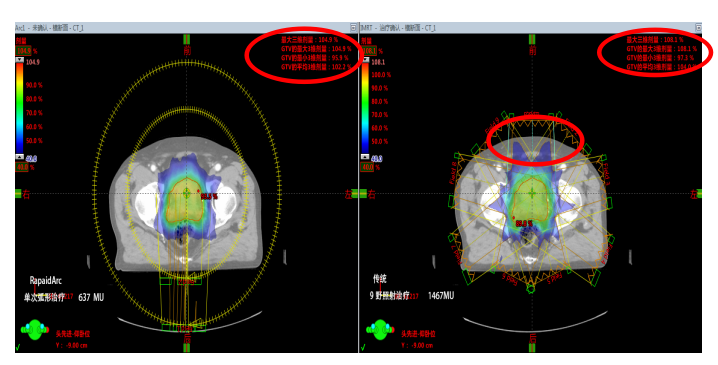

Rapid Arc(快速旋轉(zhuǎn)容積調(diào)強(qiáng)治療技術(shù))使治療時(shí)間的充分減少帶來諸多好處。首先,病人的耐受力是有限的,治療時(shí)間的縮短可以提高病人的舒適度。其次,是人體內(nèi)部器官的持續(xù)運(yùn)動(dòng),治療時(shí)間的縮短可以減小誤差提高治療的精度跟可靠性。下面以一名前列腺癌患者治愈過程為例:

1.出色的劑量分布:傳統(tǒng)9野照射治療需出1467MU而RapidArc只需637MU。在確保達(dá)到優(yōu)化劑量分布的前提下,使得機(jī)器跳數(shù)達(dá)到最?。籖apidArc相比于傳統(tǒng)動(dòng)態(tài)調(diào)強(qiáng)具有更均勻的劑量跌落和更低的最大劑量的優(yōu)勢(shì)。

2.出色的放療質(zhì)量:更少的漏射線、散射線,對(duì)患者正常組織和危及器官提供更好的保護(hù),靶區(qū)適形度更好、劑量更飽滿。

3.RapidArc實(shí)施:快速完成計(jì)劃(Eclipse治療計(jì)劃系統(tǒng))單次弧形治療大大縮短治療時(shí)間,與其他治療方式相比,治療時(shí)間的縮短,提高了病人的舒適性,避免了病人移動(dòng)造成的誤差,對(duì)不能長時(shí)間保持體位不動(dòng)的患者是一種最好的治療方式。